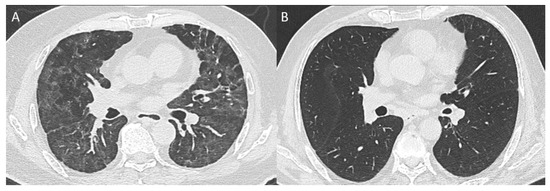

2.2. Radiological Evaluation